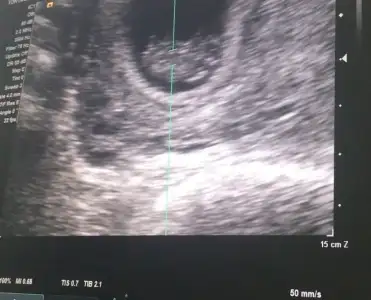

Kızlar minnoşun kalp atışlarını dinledim çok güzeldi :) sat ile uyumlu 24 mm olmuş 9+1 deyiz :KK54:

• 166B6D53-BAFF-47BD-8123-2786F8BE8D9C.webp

166B6D53-BAFF-47BD-8123-2786F8BE8D9C.webp

22,3 KB · Görüntüleme: 63